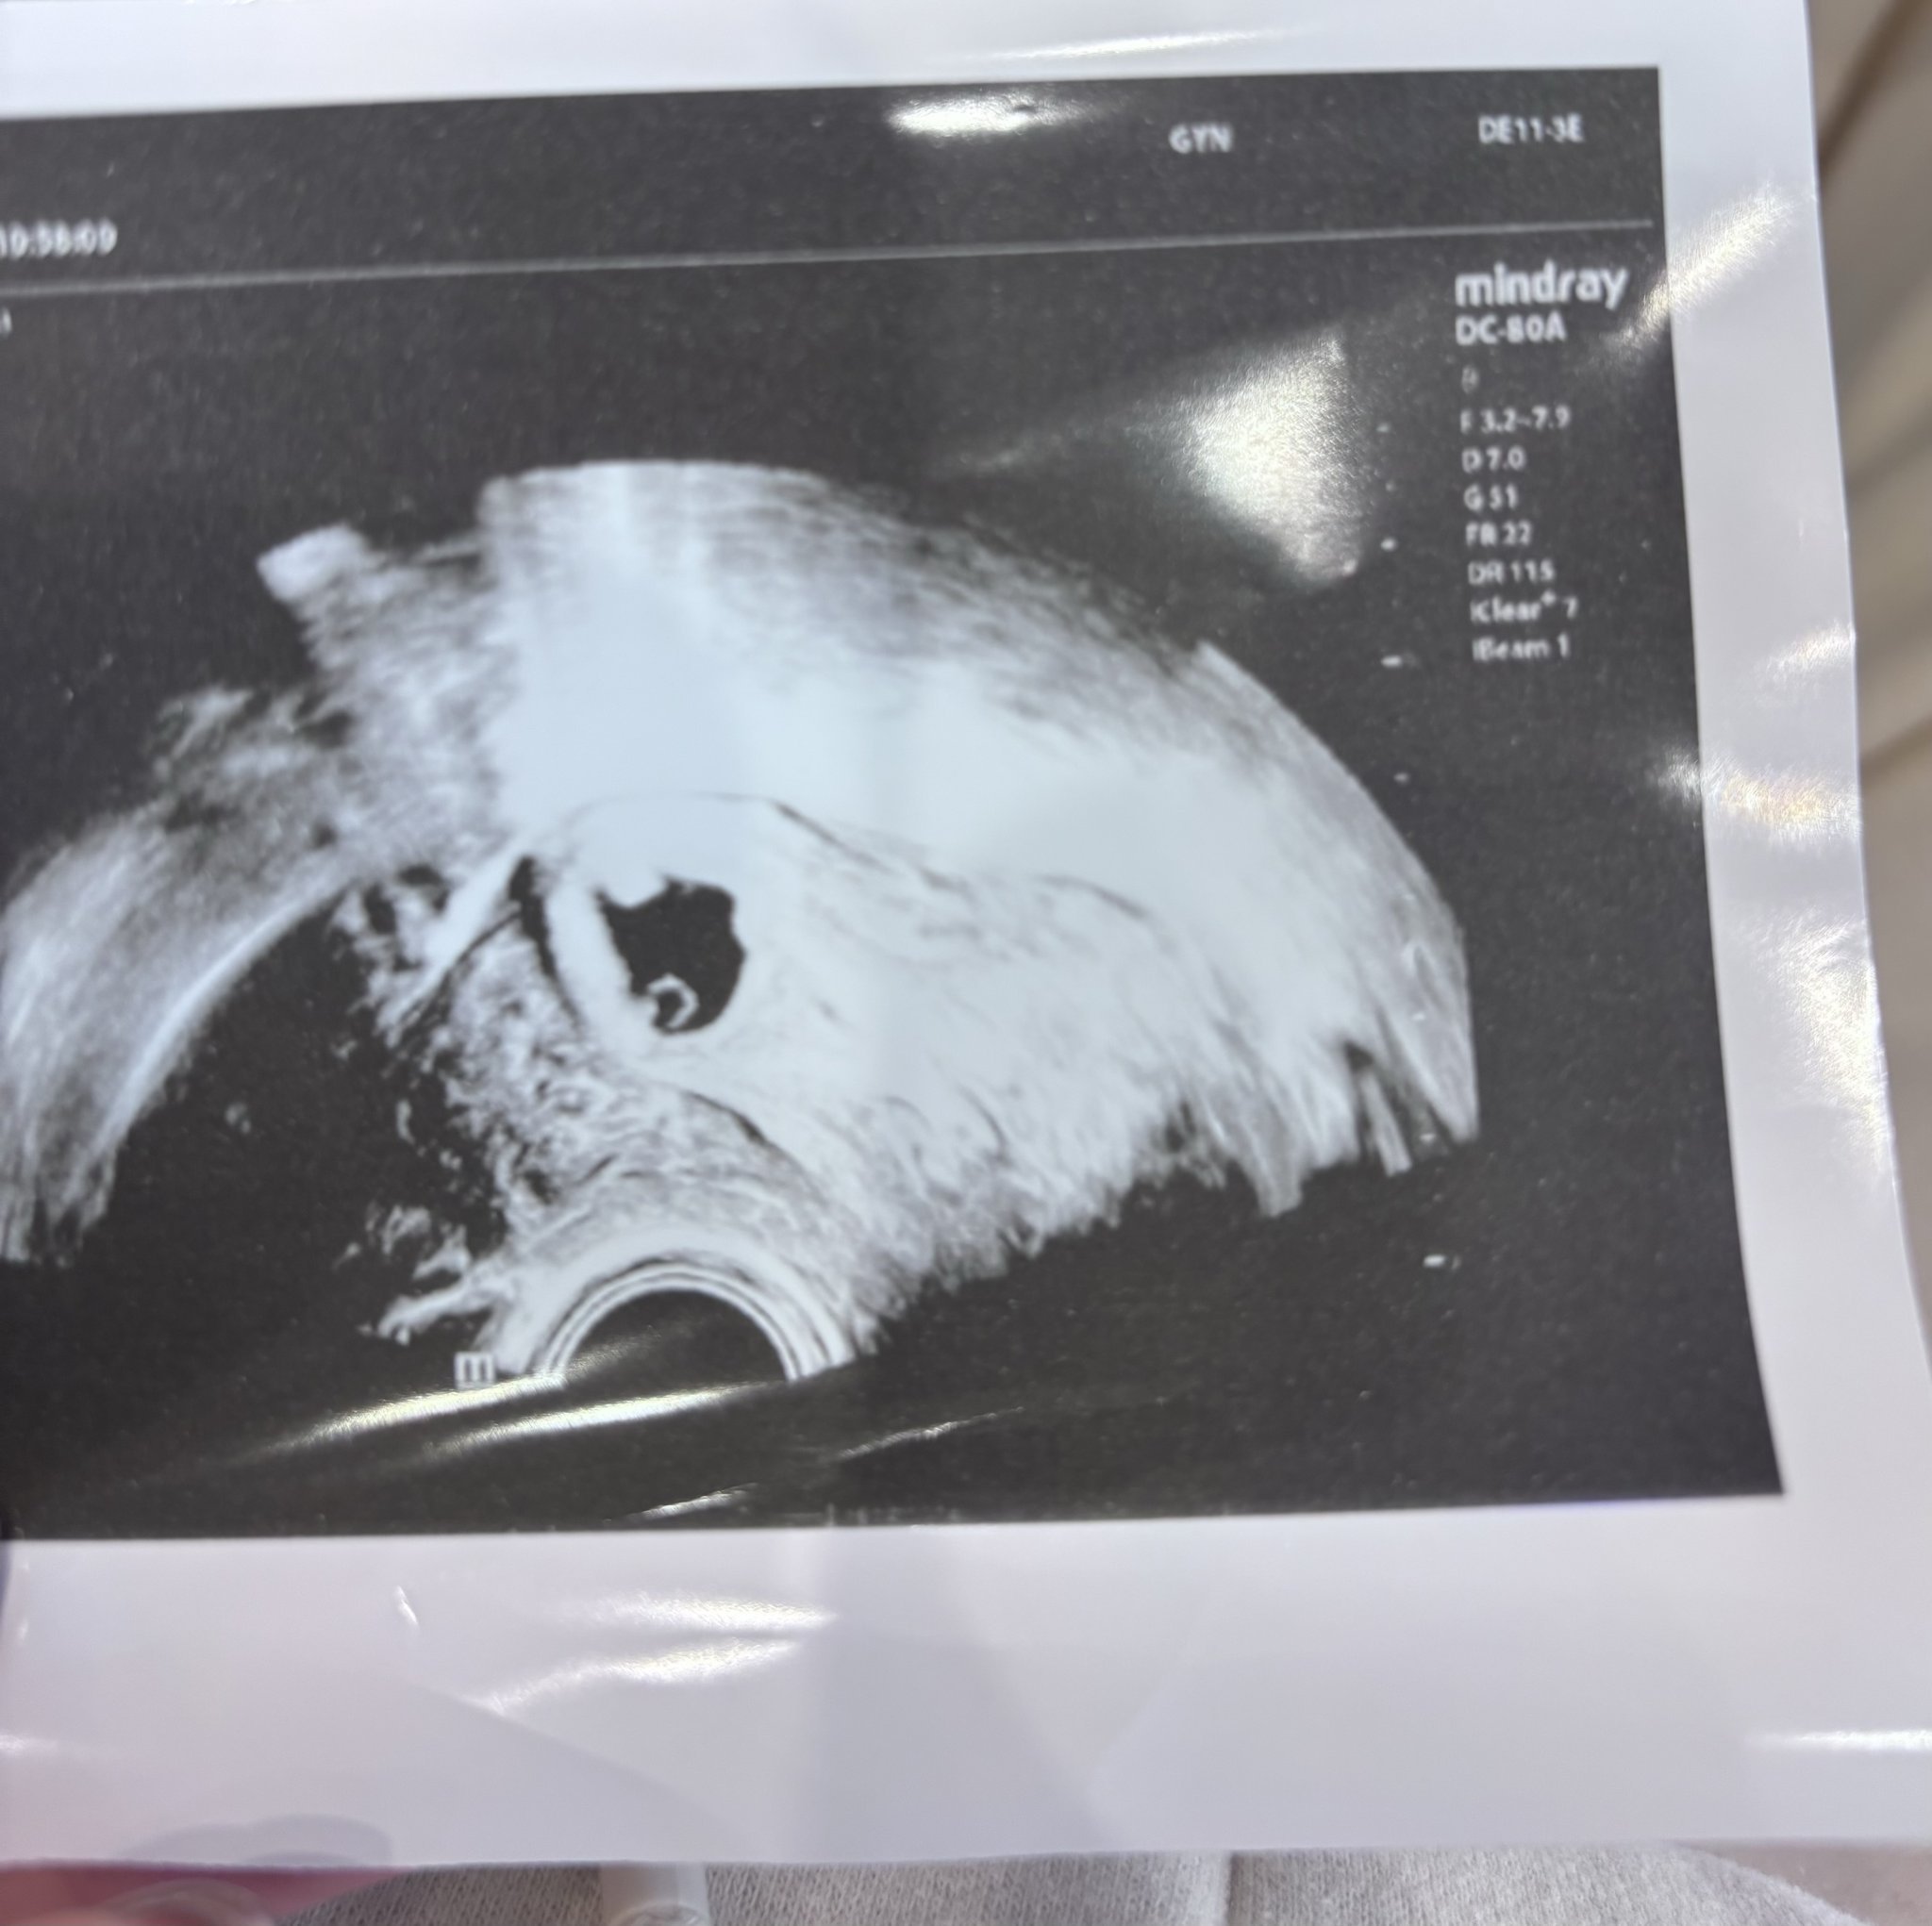

Здравейте, момичета! Днес съм 5+5 г.с. Имам две неуспешни бременности и сега треперя и се моля тази да завърши с успех. Днес бях на преглед, докторът не каза нищо притеснително, дори обратното, няма все още ембрион, но мен ме притеснява формата на сака. Вече след опита, който имам най-малкото ми прави впечатление. Интересува ме дали някой е имал подобен проблем и вашите сакчета как изглеждаха?